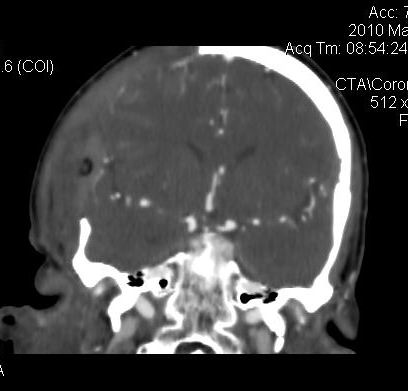

男.60岁,渐进性意识不清,ct检查双侧额颞顶部硬膜下血肿,开颅术后行脑血管cta,大脑中动脉起始部见一瘤状血管扩张。请各位老师留下宝贵意见

太常见了,报动脉瘤就可以

符合动脉瘤表现。

符合动脉瘤表现。

动脉瘤。

颅内动脉瘤。

后重建做得不是很好看,要将维蒂斯环充分显示,最好在增加一个mip。这样不好定位。

小动脉瘤

图片质量较差,是机器?

典型

符合动脉瘤的表现

动脉瘤

符合动脉瘤表现。

小动脉瘤

典型